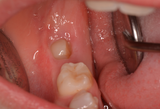

I terzi molari, conosciuti anche come denti del giudizio, a causa della loro maturazione tardiva, che avviene tra i 18 e i 21 anni, non hanno, il più delle volte, spazio sufficiente per erompere in arcata, configurandosi un quadro noto come disodontiasi. Le ragioni di ciò sono sicuramente il ridotto spazio residuale in arcata dopo l’eruzione dei secondi molari permanenti, l’inclinazione, che spesso devia il tragitto eruttivo a ridosso dei denti attigui, e la loro posizione, che non favorisce i processi di detersione naturale e meccanica con lo spazzolino, favorendo l’accumulo di placca e lo sviluppo di un quadro infiammatorio a carico del dente e dei tessuti circostanti.

Qualora il dente non sia neanche parzialmente erotto si definisce incluso. I quadri patologici che riguardano questa condizione vanno dalla pericoronite, ossia l’infiammazione del sacco pericoronario che circonda la corona del dente, allo sviluppo di un tumore odontogeno. Bisogna tuttavia verificare se, effettivamente, il terzo molare sia causa di dolore, essendo il sintomo dirimente per l’indicazione all’avulsione. Se presente, l’estrazione sarà volta alla risoluzione della sintomatologia dolorosa ed avrà scopo terapeutico. Diversamente, parleremo di indicazione profilattica, quando l’avulsione sarà mirata a scongiurare il rischio che quel dente possa dare patologie future di tipo carioso, parodontale o tumorale, o di indicazione strategica quando sarà parte integrante di una terapia ortodontica o di una riabilitazione protesica specifica.

Oltre a tenere conto dello stato di salute generale del paziente, in questo tipo di estrazione più che in ogni altra, è estremamente importante lo studio del caso e la valutazione della forma, della posizione del dente e delle sue radici rispetto ad alcune strutture importantissime, come il seno mascellare per i molari superiori e il nervo alveolare inferiore per quelli inferiori, dal cui coinvolgimento potrebbero scaturire complicanze più o meno gravi. E’ necessario dunque che il paziente si sottoponga ad esami radiologici come l’OPT, spesso insufficiente in questo tipo di chirurgia o alla TC Cone Beam, che si presta perfettamente a mostrare l’esatta posizione del dente ed i suoi rapporti, in base ai quali il chirurgo valuterà la difficoltà dell’intervento e sarà in grado di prendere dovute precauzioni.

L’intervento è eseguibile ambulatorialmente in anestesia locale e prevede l’allestimento di una breccia chirurgica fino alla visualizzazione del dente. Si esegue una fase di osteotomia, ossia la rimozione, con strumenti rotanti e/o piezoelettrici, dell’osso che ostacola lo scorrimento della corona per permettere la sua mobilizzazione.

A seconda del grado di mobilità del dente, la sua avulsione sarà completata con l’uso di leve e/o pinze.

Qualora il dente risulti essere tenacemente bloccato, sarà tagliato e rimosso in più parti. La cavità ossea residua sarà opportunamente disinfettata e saranno rimosse eventuali lesioni periapicali, in modo da favorirne il riempimento con nuovo tessuto osseo. L’intervento termina con l’applicazione di punti di sutura.